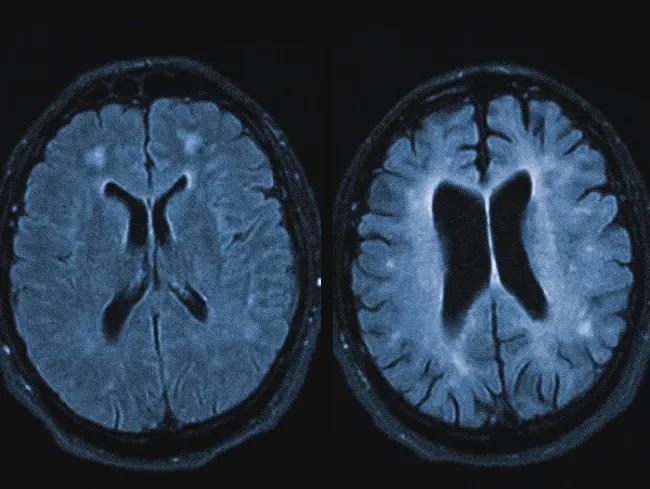

Биологически это связано с дисбалансом дофамина: гиперактивность в мезолимбическом пути вызвала галлюцинации, но в данном случае этот "дофаминовый шторм" был направлен на спасение. Как только внешние триггеры стресса исчезли, мозг самостоятельнр деактивировал этот сложный программный слой, "разобрал доски" и восстановил нормальную синаптическую передачу.